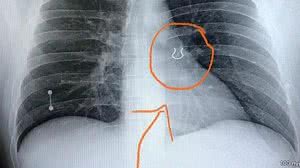

Médicos encontram piercing de nariz perdido há cinco anos alojado no pulmão de paciente